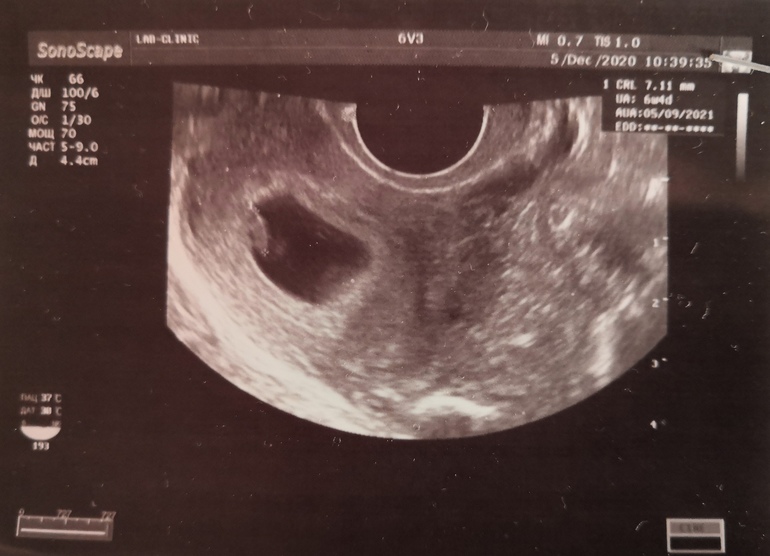

Сходила сегодня на первое УЗИ. Ттт всё хорошо, сердечко дали послушать. По месячным 7 недель 1 день, по УЗИ ставят 6 недель 4 дня. Мне конечно без разницы кто мальчик или девочка, главное чтоб здоровенький. Но интересно же, прям любопытство распирает.

УЗИ трансвагинальное было.